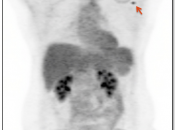

Extravasation of Injected FDG

FDG is injected intravenously. As many cancer patients have challenging venous access issues, partial extravasation of FDG during injection is not uncommon (an estimated 10% of patients have evidence of extravasation on their PET images).

Extravasation of FDG at the time of the intravenous injection can result in false positive interpretations due to:

- Focal intense uptake at the injection site.

- Linear uptake along the lymphatic channels within the arm (appearing as long vessels).

- Focal uptake in small ipsilateral axillary nodes.

If these nodes are enlarged, be cautious before dismissing them as “injection-related”. We have seen more than one case of a radiologist calling axillary nodes “injection-related”, when the patient was injected in the opposite arm.

If the volume of extravasation is large enough, it can result in a significant reduction of circulating FDG available for tumoral uptake, resulting in false negative results (“Sponge Effect”, discussed here).